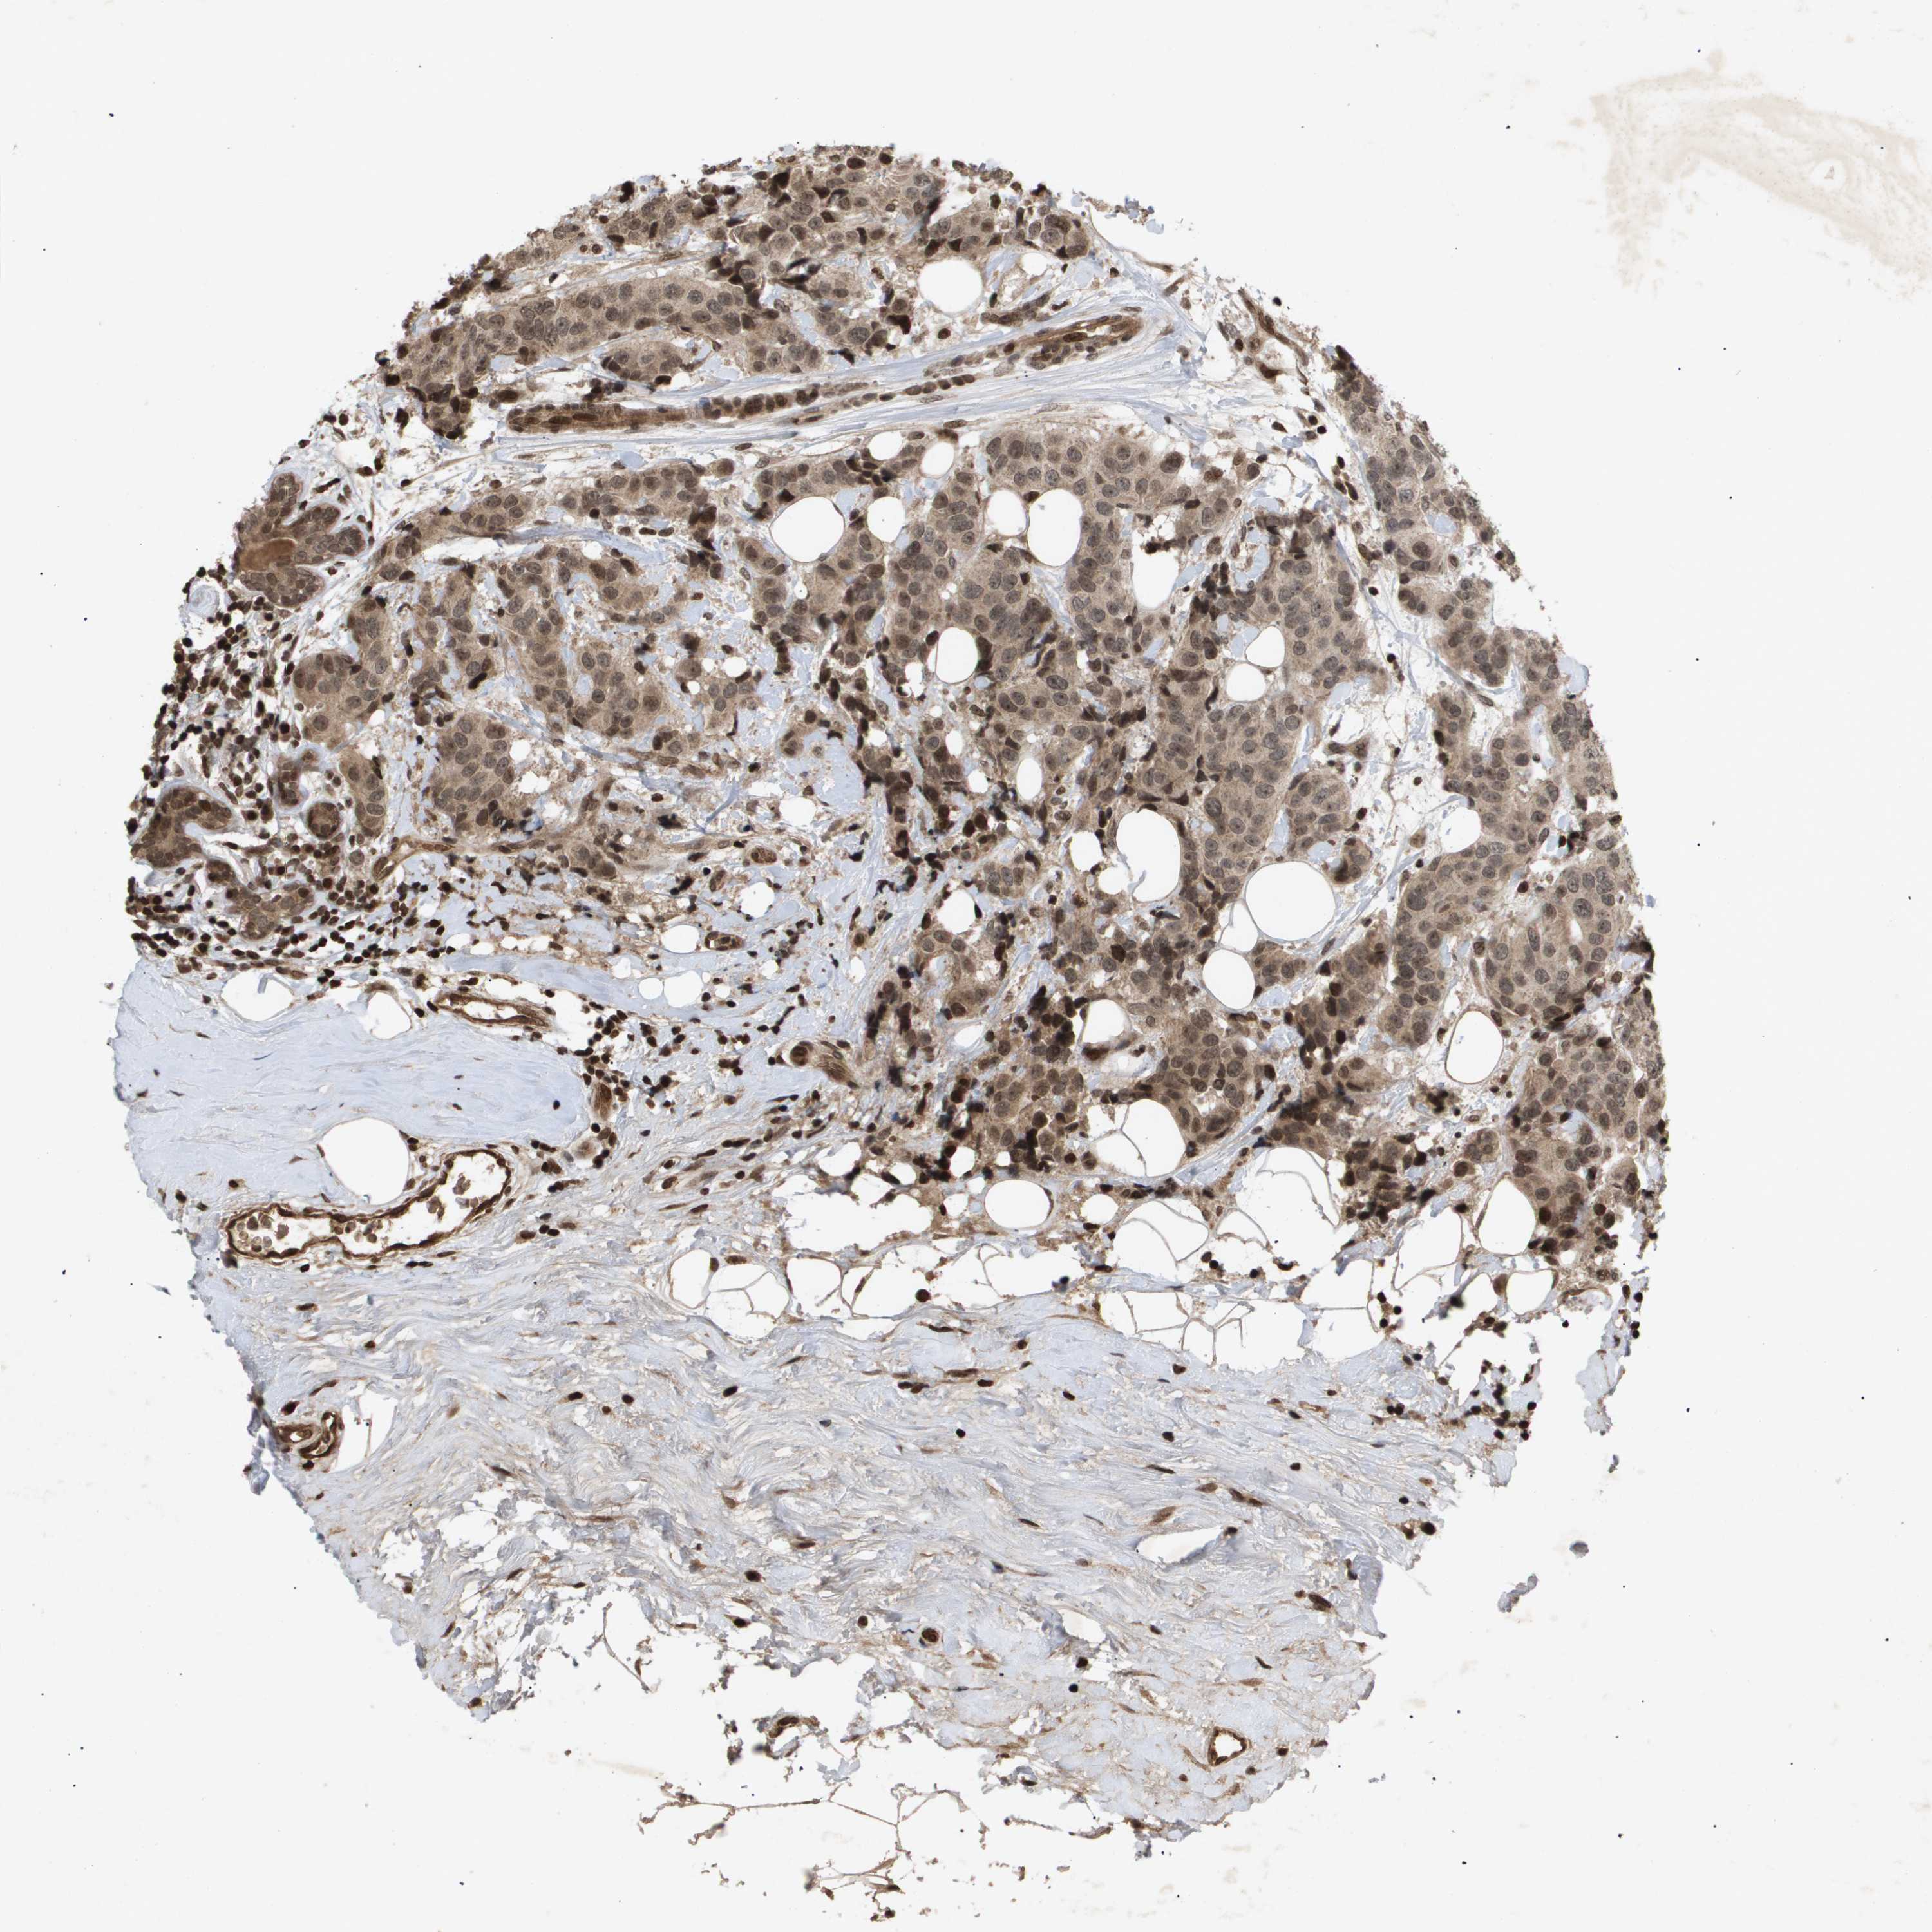

CANCER BREAST CANCER Show tissue menu

BRCA TCGA BRCA VALIDATION PROTEIN EXPRESSION

Breast cancer

Human cancer

HSPA6 is not prognostic in Breast Invasive Carcinoma (TCGA)